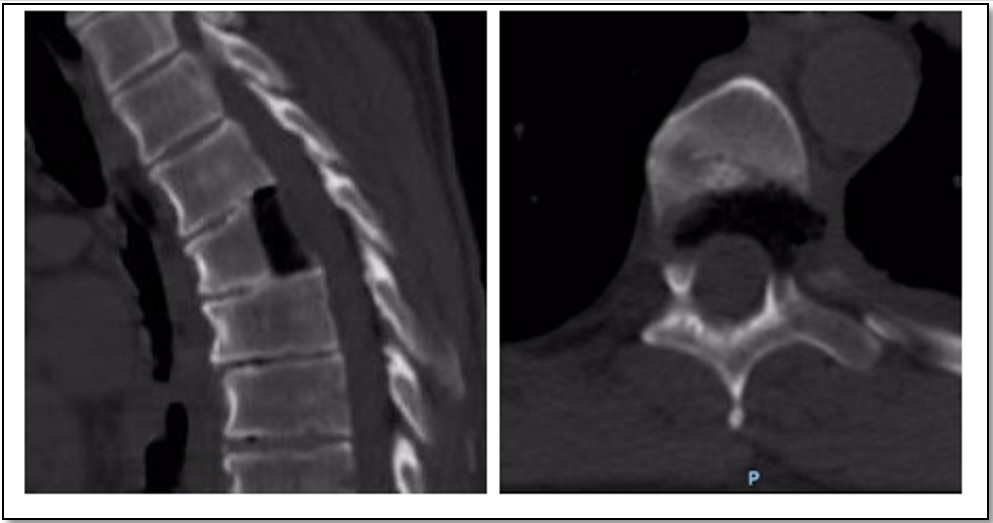

We present the case of a 64-year-old male with spinal compression symptoms, central disc herniation calcified at the fifth thoracic vertebra, which migrated to the lower end of the sixth thoracic vertebra. Diagnosis was clear for spinal cord compression. Partial posterior corpectomy of the sixth vertebra was performed with a minimally invasive transthoracic transpleural lateral approach and without additional fixation. The patient had a good outcome on follow-up, without progression of neurological symptoms or residual rib pain.